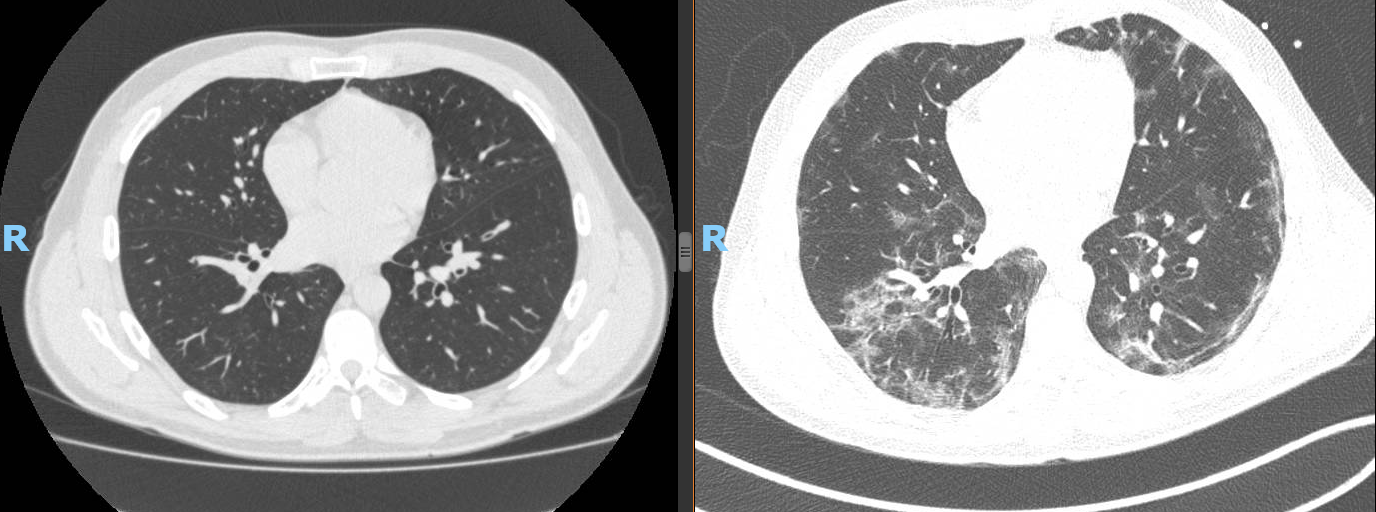

Após minha equipe ter atendido mais de 1.000 (isto mesmo mil) casos de Covid, nestes quase 2 anos de pandemia, sem nenhum óbito, eu imaginaria que saberia dizer alguma coisa sobre o que devemos esperar. Não sei e efetivamente não tenho argumentos para defender algumas das muitas especulações que escuto, como: O vírus esta ficando “bonzinho” e vai se tornar […]

Como disse Sócrates: “Tudo que sei, é que nada sei”, e é assim que me sinto (mesmo a equipe que lidero tendo cuidado de cerca de 800 casos de COVID-19) em relação a este vírus. Esta variante (Ômicron) parece não ser bem comportada do ponto de vista de não se importar se: Você já teve ou não COVID-19 (estou vendo […]